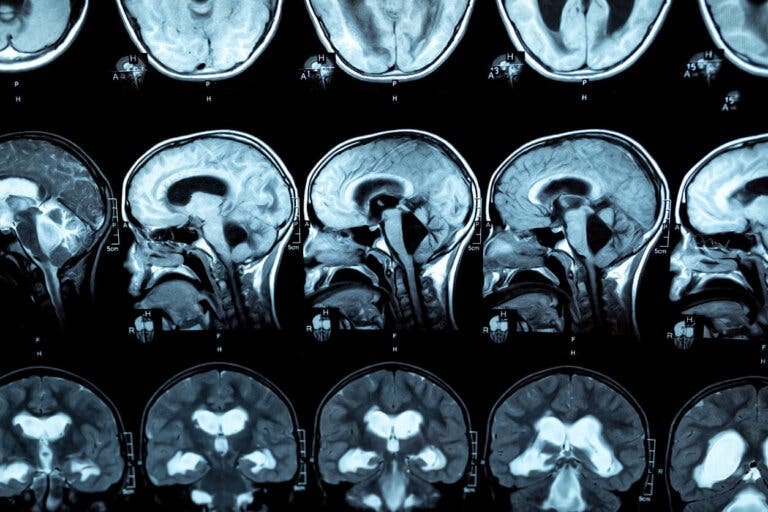

Para el diagnóstico de esta patología se realiza una resonancia magnética, de modo que se observen las lesiones en el cuerpo calloso. Al respecto, en las investigaciones se señala que las personas con trastorno por consumo de alcohol evidencian reducción en el grosor anterior, medio y posterior del cuerpo calloso, así como variaciones en tamaño del lóbulo frontal y de los surcos corticales.